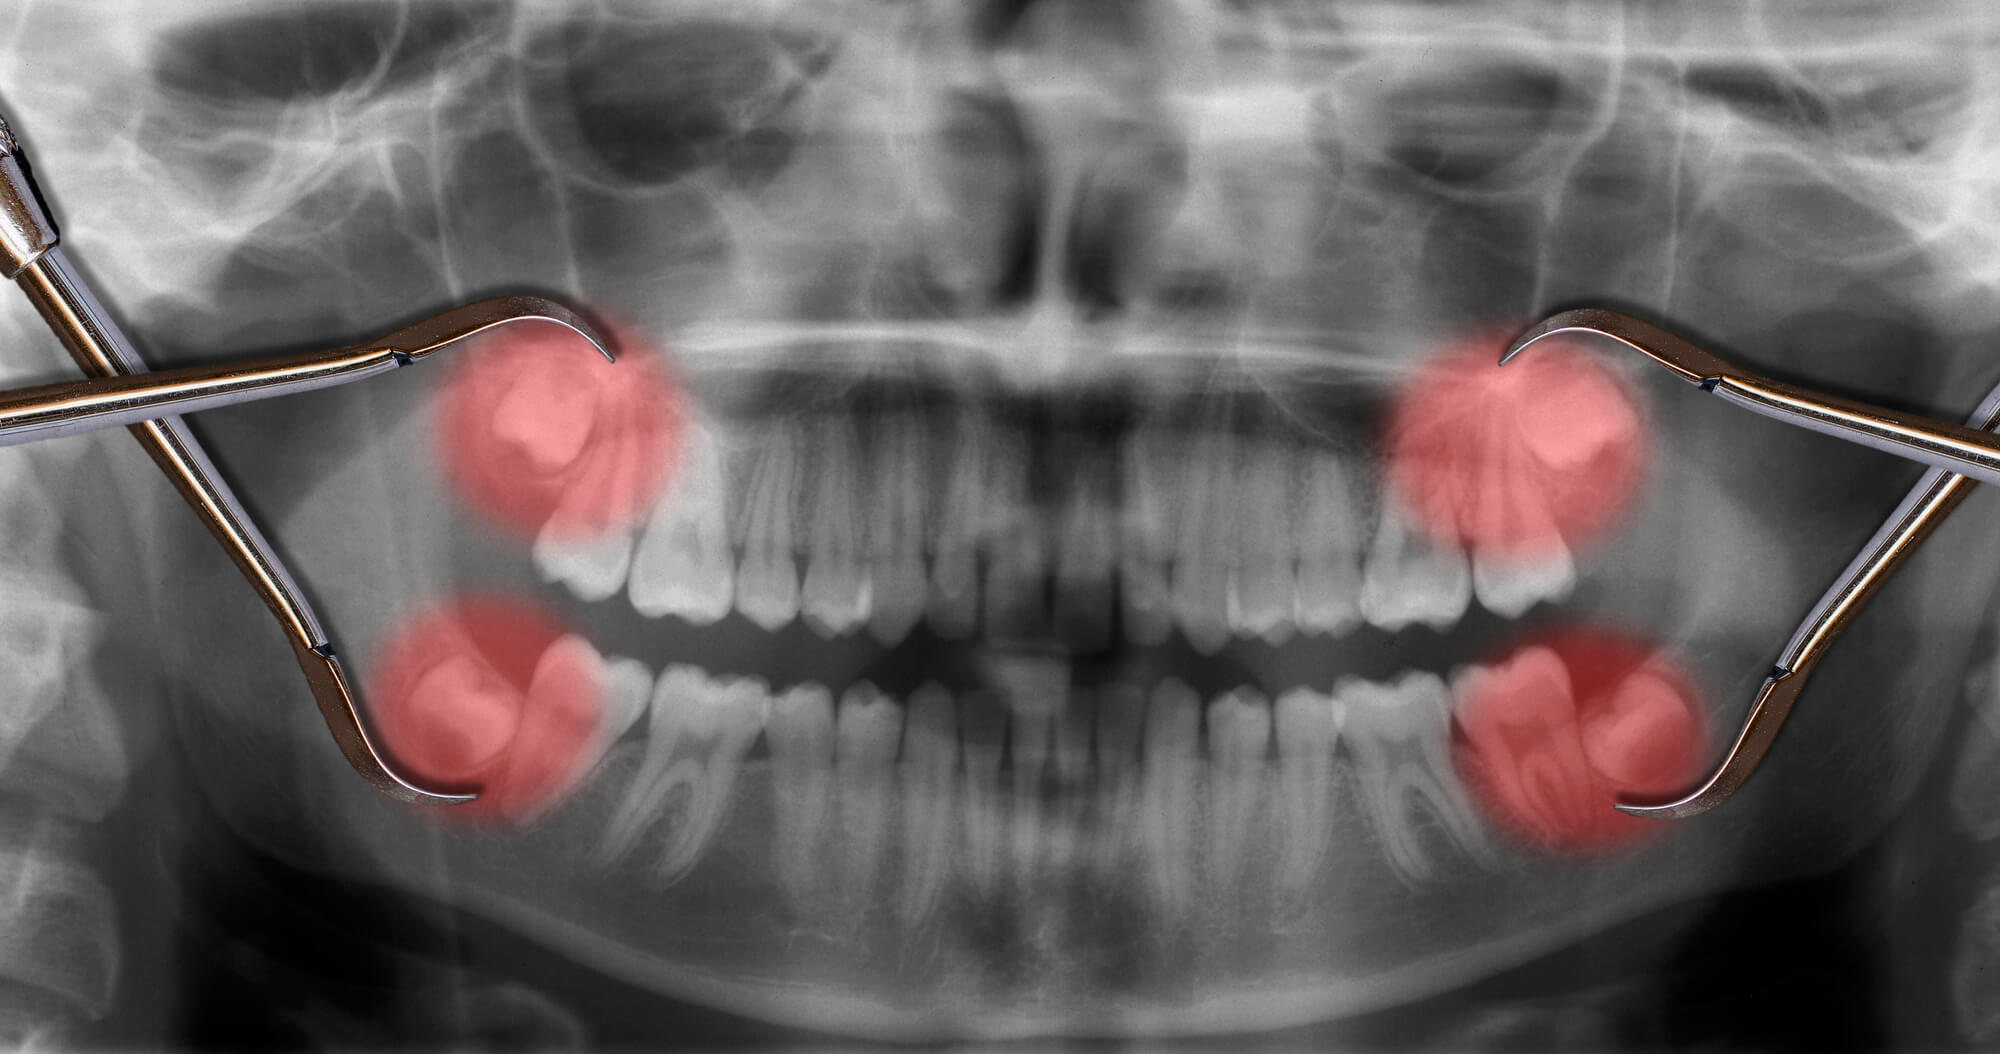

Wisdom teeth that have become impacted are typically angled or horizontally aligned. They arrive misaligned as a result of this. They can put pressure on your other teeth or their roots, causing pain and possibly tooth movement.

Wisdom teeth don't show up until they start to erupt. That's why x-rays are an essential part of your teen's dental check-ups. They enable your dentist to track the emergence of your wisdom teeth.